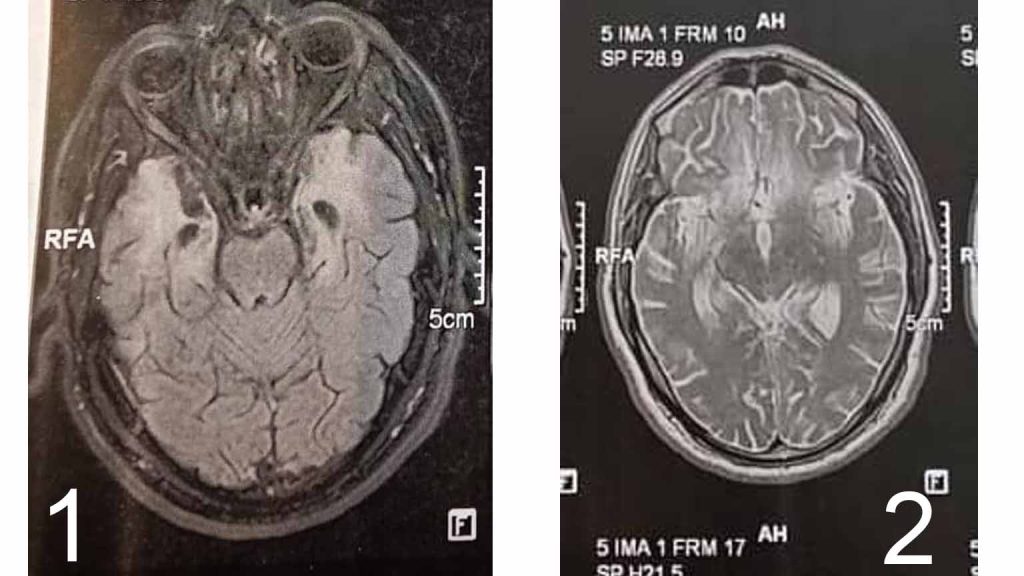

در MRI مغز، ضایعات هیپرسیگنال گسترده در لوبهای تمپورال و اینفرافرونتال دوطرفه دیده می شود. ( تصاویر ۱ الی ۴ )

در MRI مغز، ضایعات گسترده در لوبهای های تمپورال دو طرفه و اینفرافرونتال داشت که مشابه با درگیری قبلی ام آر آی بود.

بیمار فوق با توجه به اینکه، الگوی ام آر آی دوم مشابه با ام آر آی اول بود و از سمتی پانل آنتی بادی های اوتوایمیون کاملا منفی شدند، تشخیص HSE داده شد و علایم نورولوژی بیمار، به عوارض نورولوژی بعد از عفونت هرپس اطلاق شد.